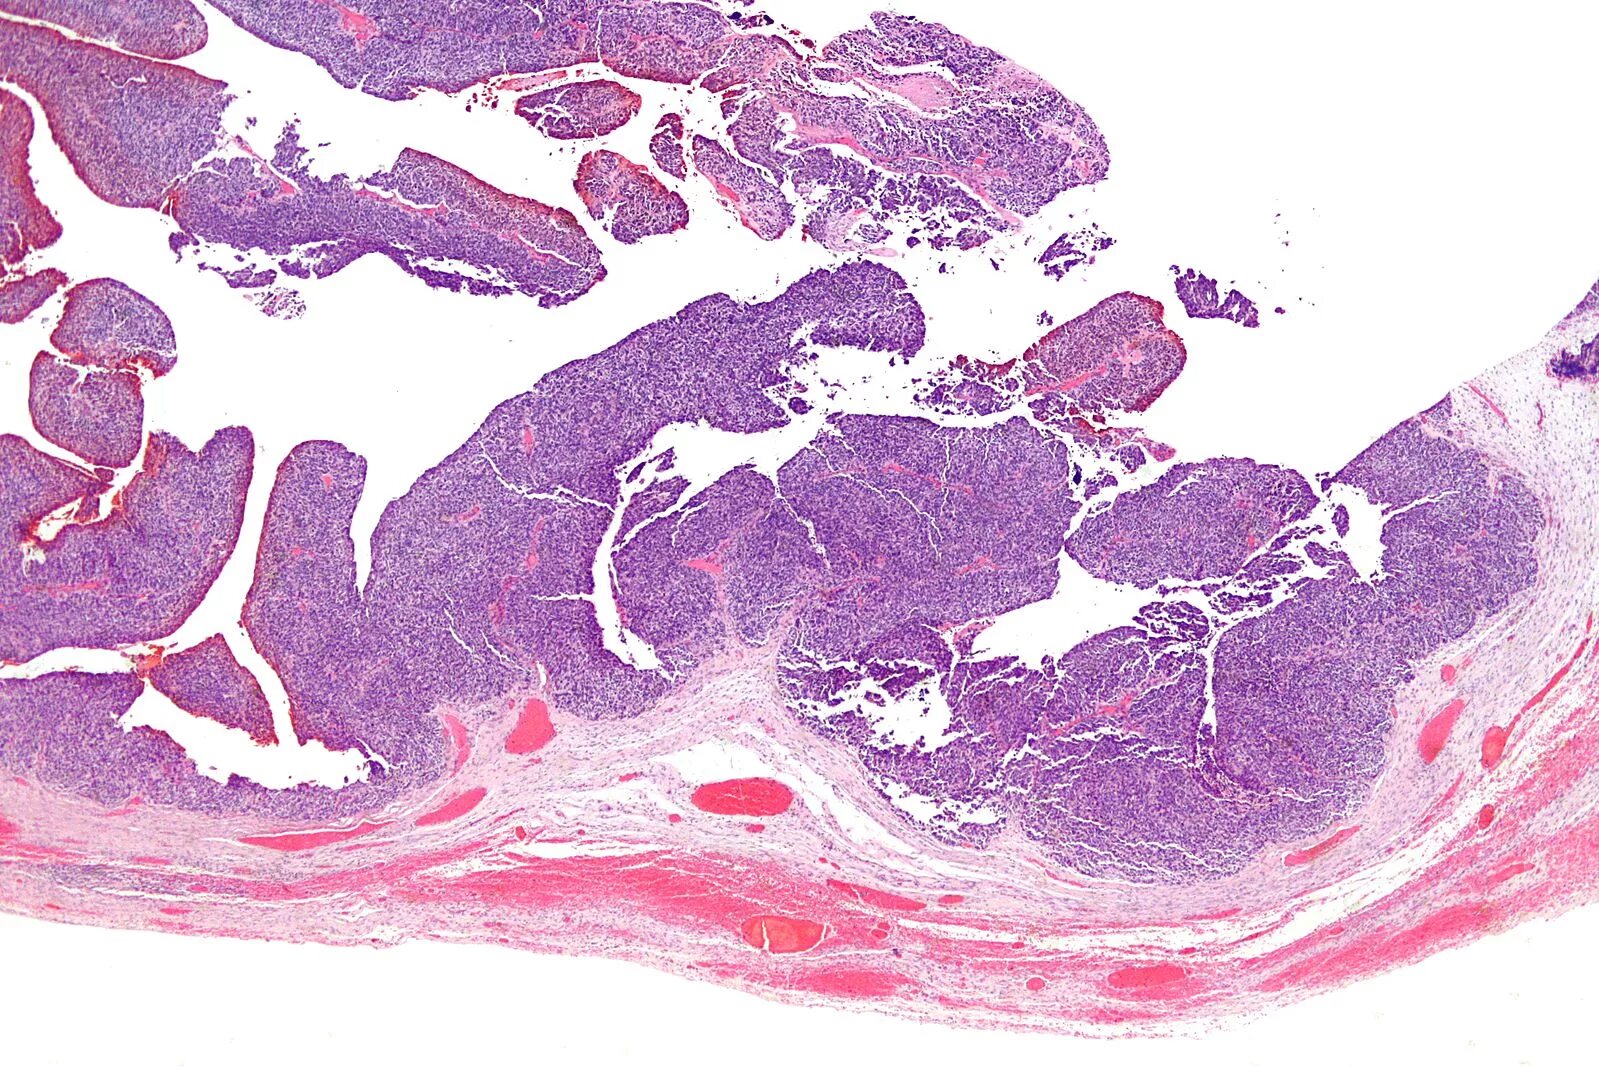

Гистология цистаденомы